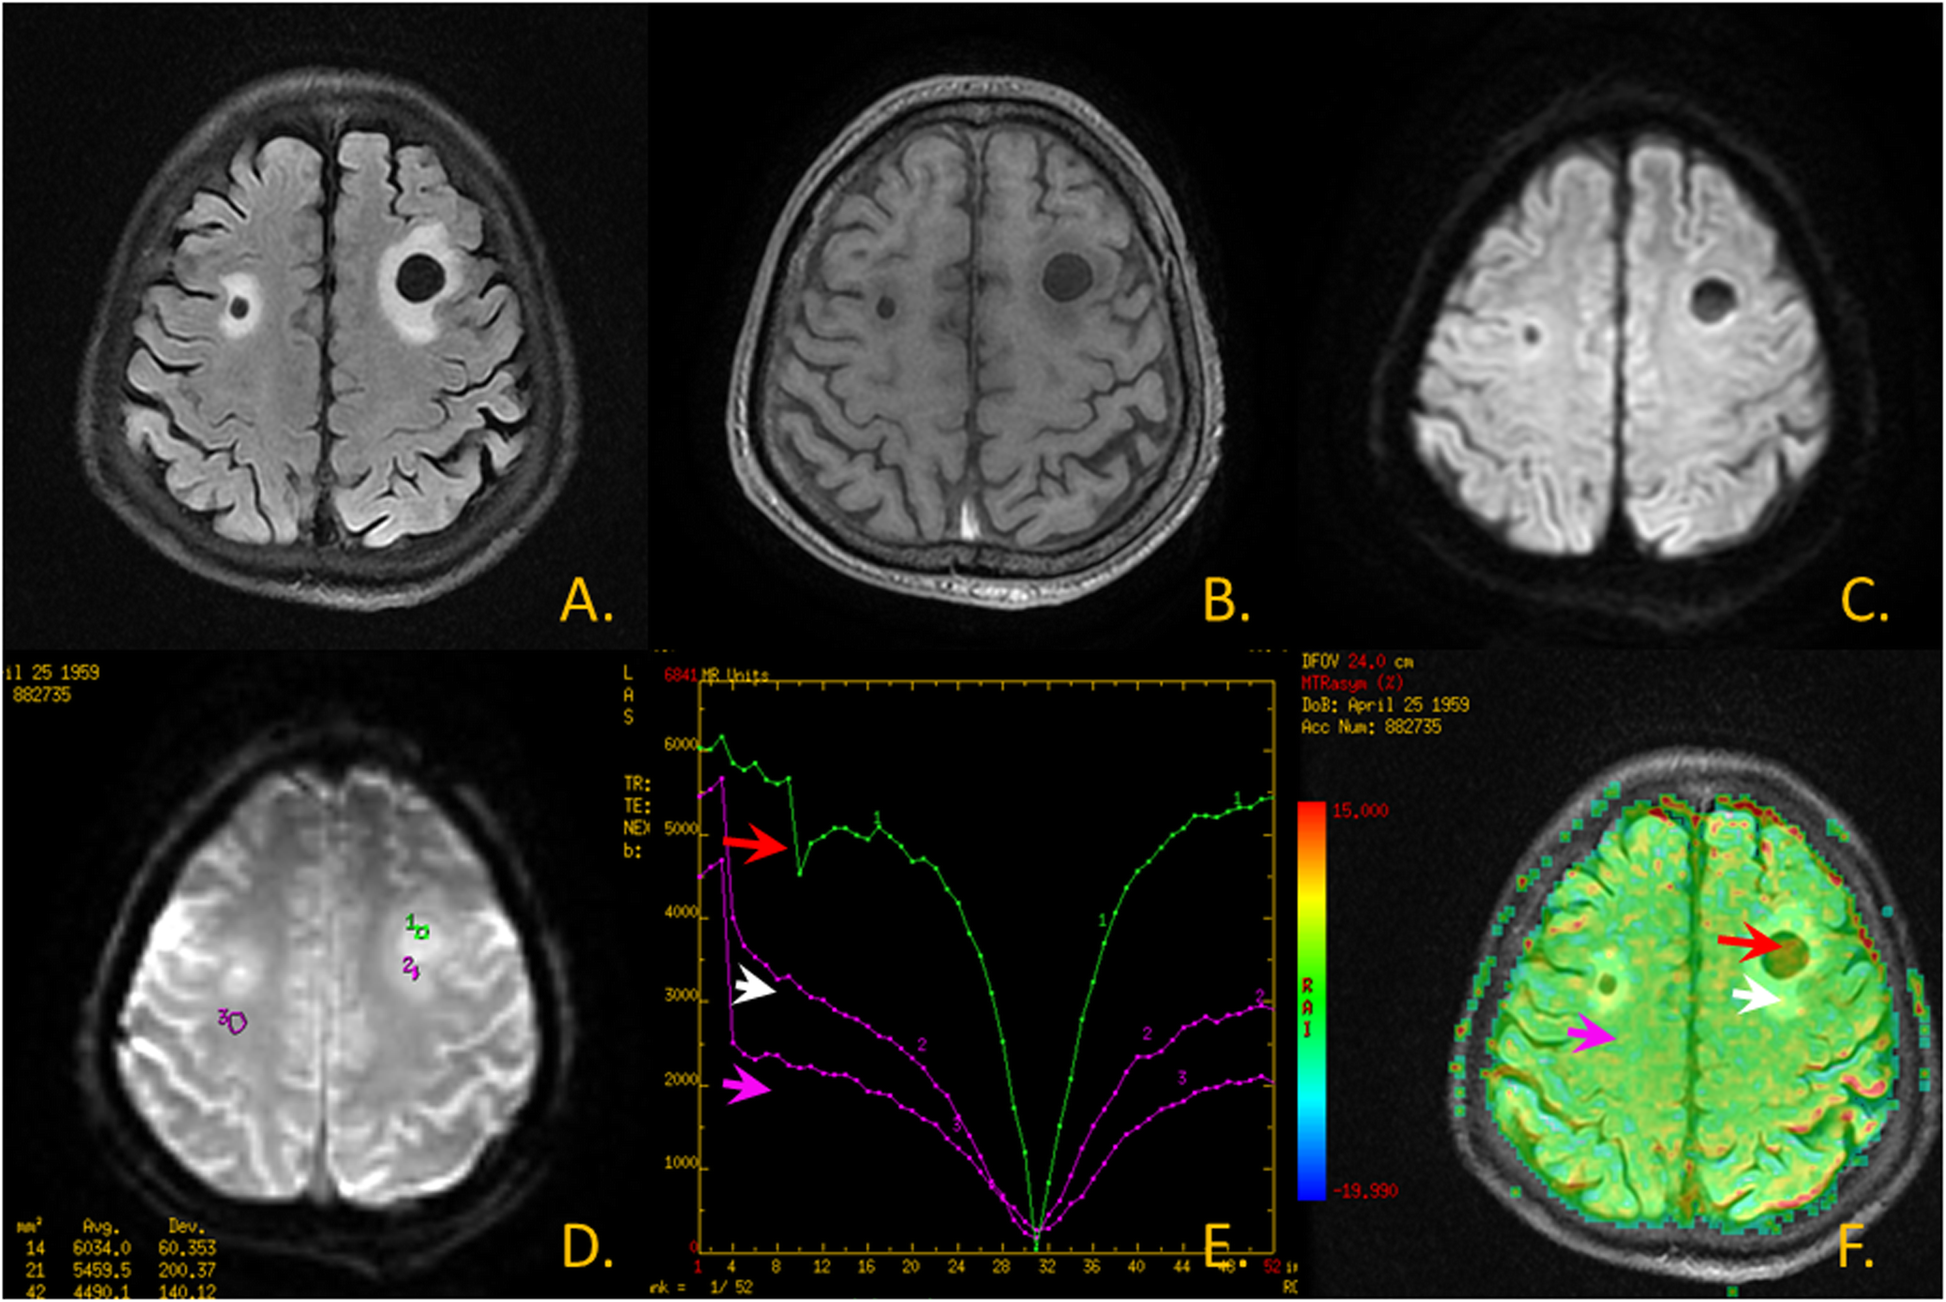

Fig. 2

Metastatic tumor images. a.T2 FLAIR image; b.T1WI; c. DWI; d. CEST Original map; e. CEST Z spectrum: The red arrow area is shown as lesion-parenchymal areas, The white arrow area is shown as edema areas and The pink arrow area is shown as non-focus areas; f. CEST MTR map and T2 FLAIR image fusion: The red arrow area is shown as lesion-parenchymal areas, The white arrow area is shown as edema areas and The pink arrow area is shown as non-focus areas